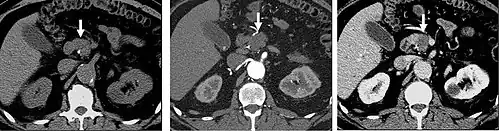

Late arterial phase

The late arterial phase is timed to correspond to the peak concentration of contrast material in highly vascular tumors and is performed approximately 20–35 seconds after the injection of intravenous contrast. Early arterial phase imaging is predominantly utilized for angiography and will be discussed separately. Late arterial phase imaging is almost always performed in conjunction with other phases (e.g. portal venous phase) to allow more complete characterization of any identified abnormalities (figure 4). The primary indication for a late arterial phase is for the evaluation of hypervascular tumors of the liver such as hepatocellular carcinoma or hypervascular metastases (figure 4). Typical hypervascular tumors for which this would be used include: hepatocellular carcinoma; renal cell carcinoma; melanoma; carcinoid/neuroendocrine tumors; some sarcomas; choriocarcinoma; and thyroid carcinoma. Although a "hypervascular", biphasic evaluation would generally be used for these patients, note that a single phase is often adequate for follow up imaging.

Liver masses

When evaluating hepatic masses, it can be advantageous to have both late arterial and portal venous phase images (biphasic imaging, figure 4) since some tumors enhance briskly during the arterial phase (hepatocellular carcinoma, hepatic adenoma, follicular nodular hyperplasia (FNH), and hypervascular metastasis), but may be occult or difficult to characterize on portal venous phase imaging alone (figure 6). However, it should be stressed that the addition of late arterial phase images is only indicated if one of these tumors is suspected, or if there is a need for further characterization of a hepatic mass, since the large majority of patients will not benefit from the addition of this phase. In addition, if there is a need to definitively characterize a hepatic mass, MRI is generally more sensitive and specific, with no associated radiation dose.